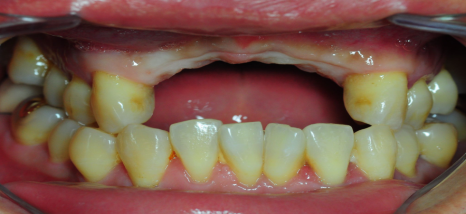

[스마일디 임플란트 사례 중 일부]

치료기간: 23.12.25일-24.06.28 (약 6개월)

진행한 치료: 발치 후 염증치료, 골이식과 임플란트2개 식립후 브릿지

*치료 전후 사진은 환자의 동의하에 게재하였으며, 동일한 환경과 조건에서 촬영된 전후 사진입니다.